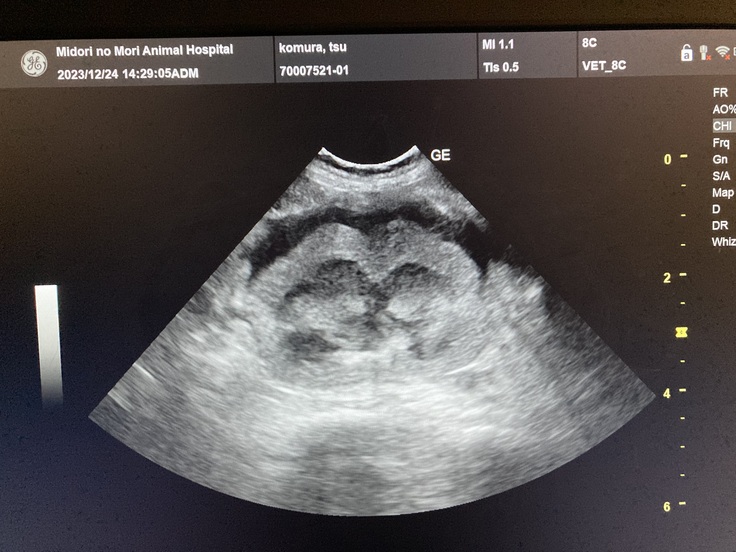

病院に到着して問診と診察を受け、食欲不振の原因が分からないので血液検査とエコー検査をしてもらい、原因が判明しました。

血液検査の結果で腎臓の数値が上がっていて、炎症もしているとの事でした。

左右両方の腎臓のエコー写真も見せて頂きました。

この影響で食欲不振になっていると担当獣医師が教えてくれました。